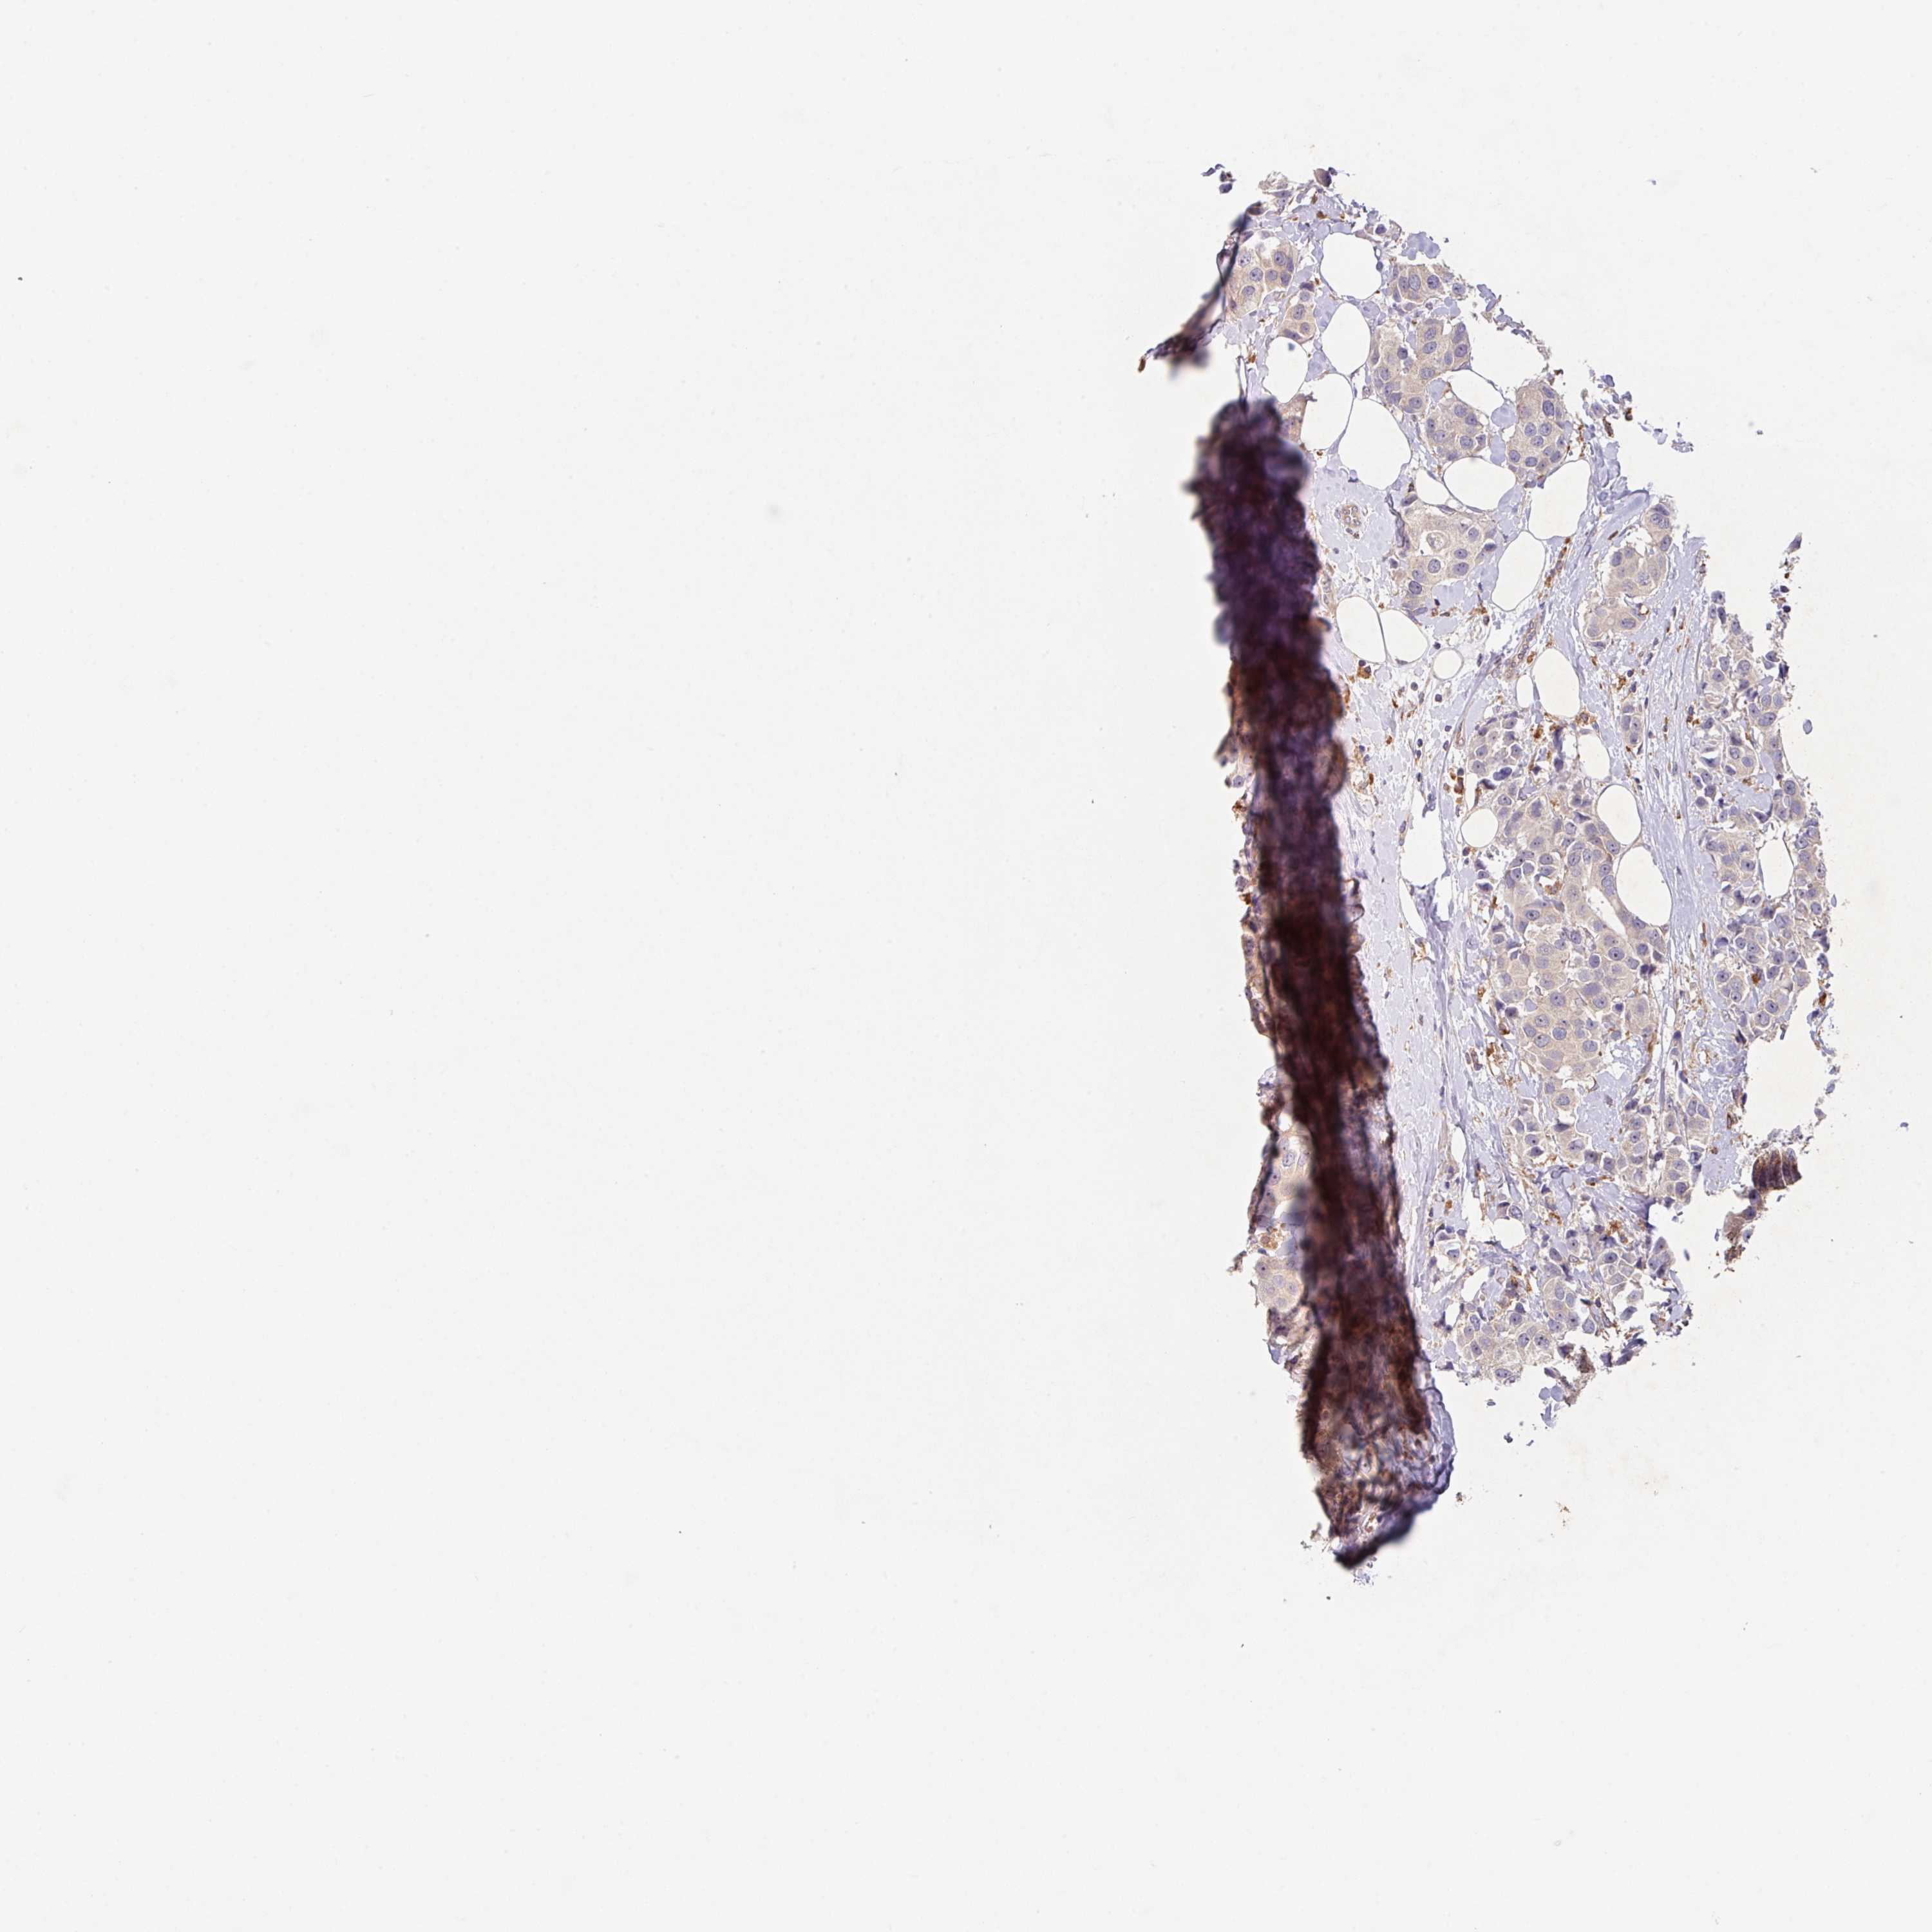

CANCER BREAST CANCER Show tissue menu

BRCA TCGA BRCA VALIDATION PROTEIN EXPRESSION

Breast cancer

Human cancer

Breast invasive carcinoma